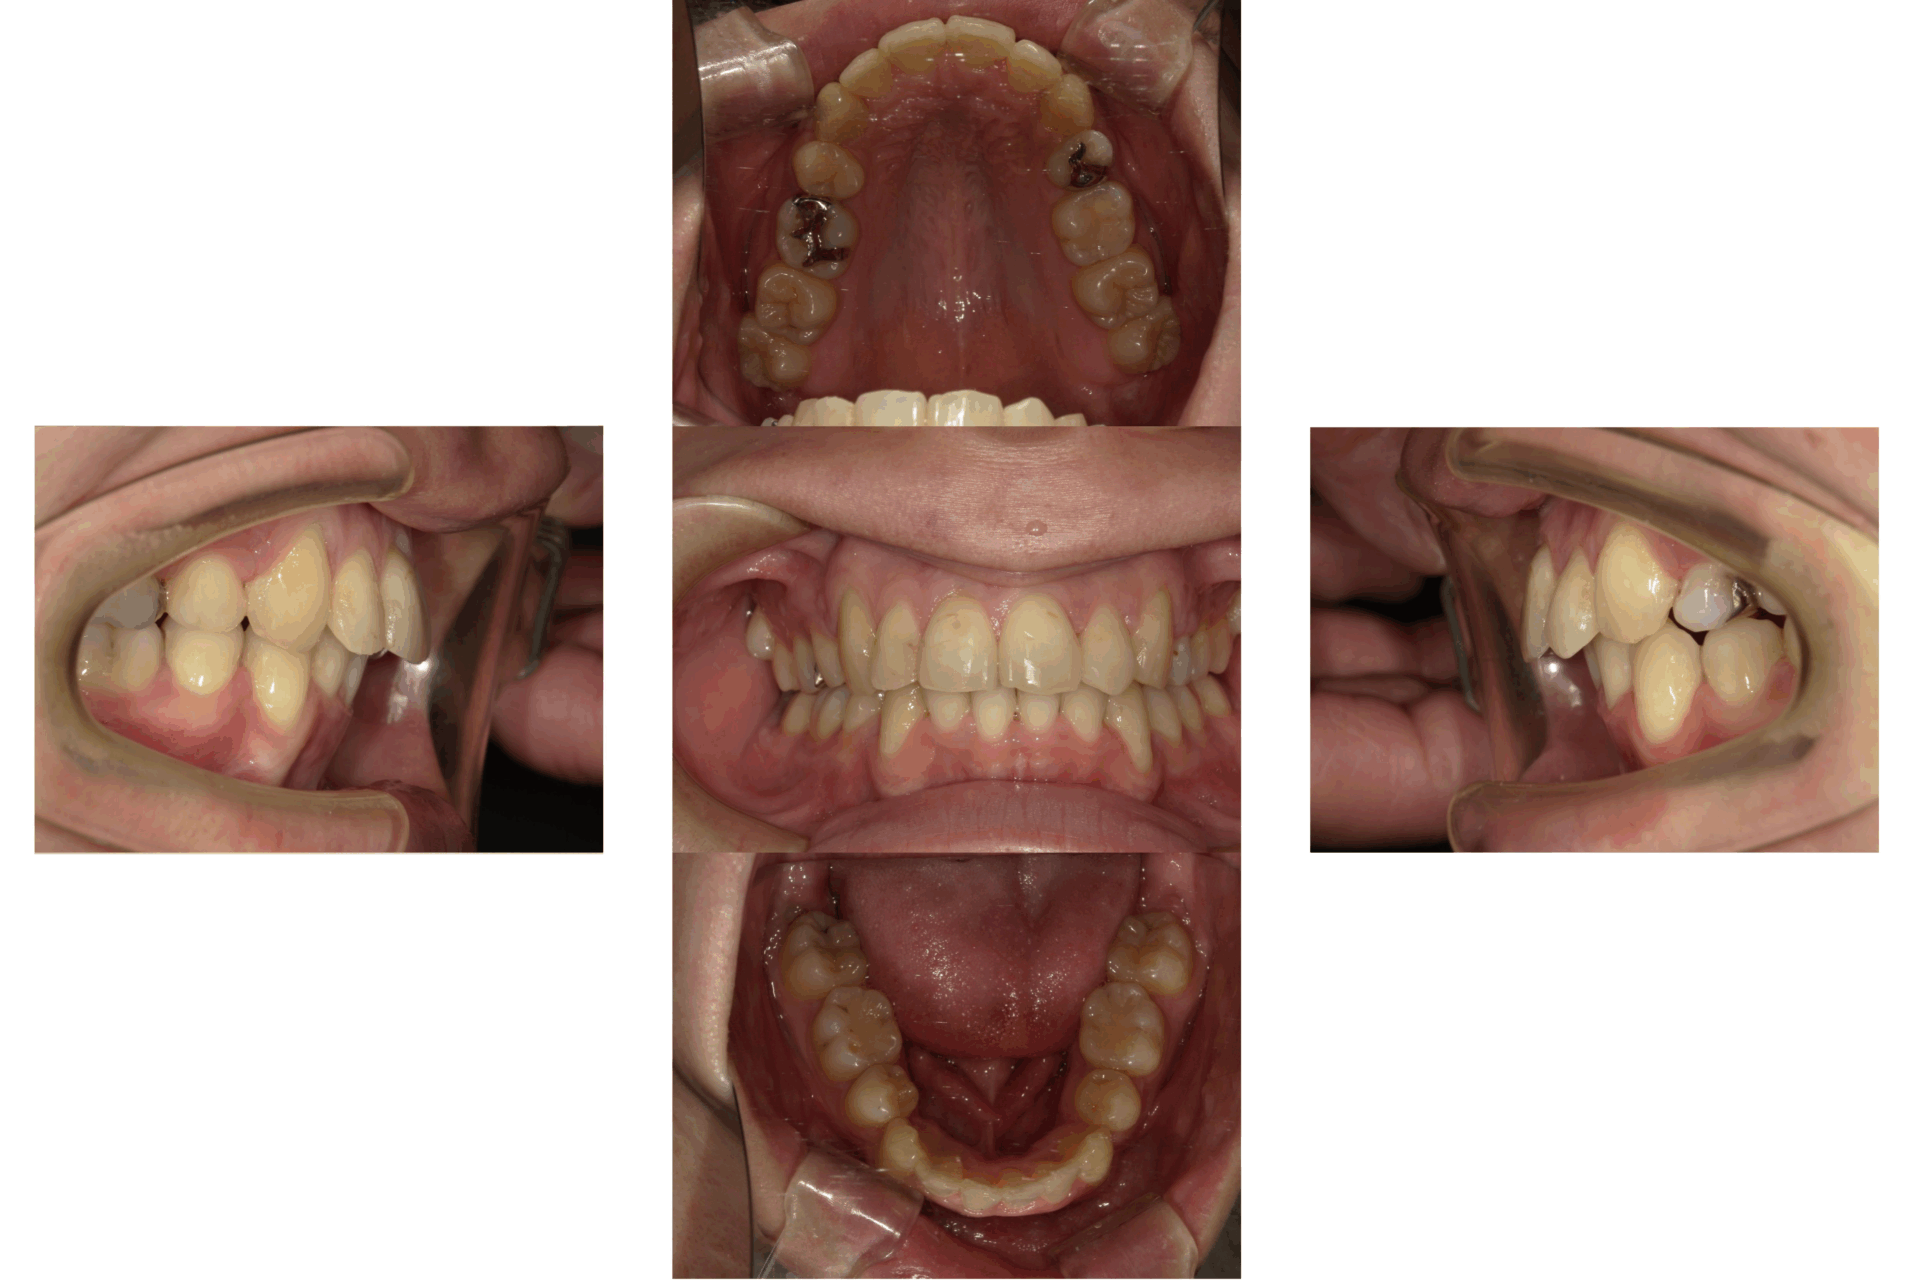

20代、男性、ワイヤー

| 施術内容 | 主訴:でこぼこで食べ物がよく挟まる。虫歯や歯肉炎に悩まされてきた。 詳細:ワイヤー矯正での歯並び改善 とても磨きやすくなったと満足されてます。 |

|---|---|

| 治療期間 | 16ヶ月(2/3現在 治療終了) |

| リスク・副作用 | ■リスク・副作用 ・治療の初期段階では、痛みや不快感が生じやすくなりますが、一週間前後で慣れます。 ・歯の動き方には個人差があるため、予想された治療期間より延長する場合があります。 |

| 費用 | ワイヤー矯正 60万円(税込660,000円) |